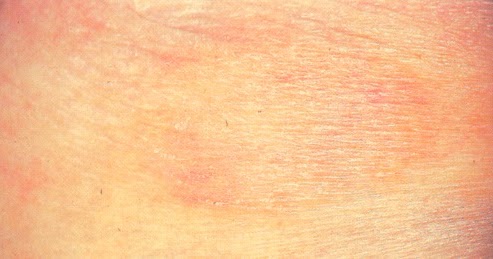

Colpisce generalmente soggetti giovani, sotto forma di un’eruzione di macchie rosa, del diametro di 3-mm, che si ispessiscono, inscuriscono e ricoprono di squame spesse. L’eruzione, localizzata agli arti e ai fianchi, ha una durata di 2-settimane. Separatamente, viene evidenziata la parabsoriasi acuta di Haberman-Much. Parapsoriasi Trattamento. Generalmente, il decorso è lento, più raramente risulta aggressivo.

La parapsoriasi è un gruppo di malattie con eziologia sconosciuta (cioè causa). Appare come macchie giallastre o marroni, che hanno bordi chiari e talvolta forme irregolari. Scopri il significato del termine medico PARAPSORIASI sulle pagine del dizionario di abcsalute.